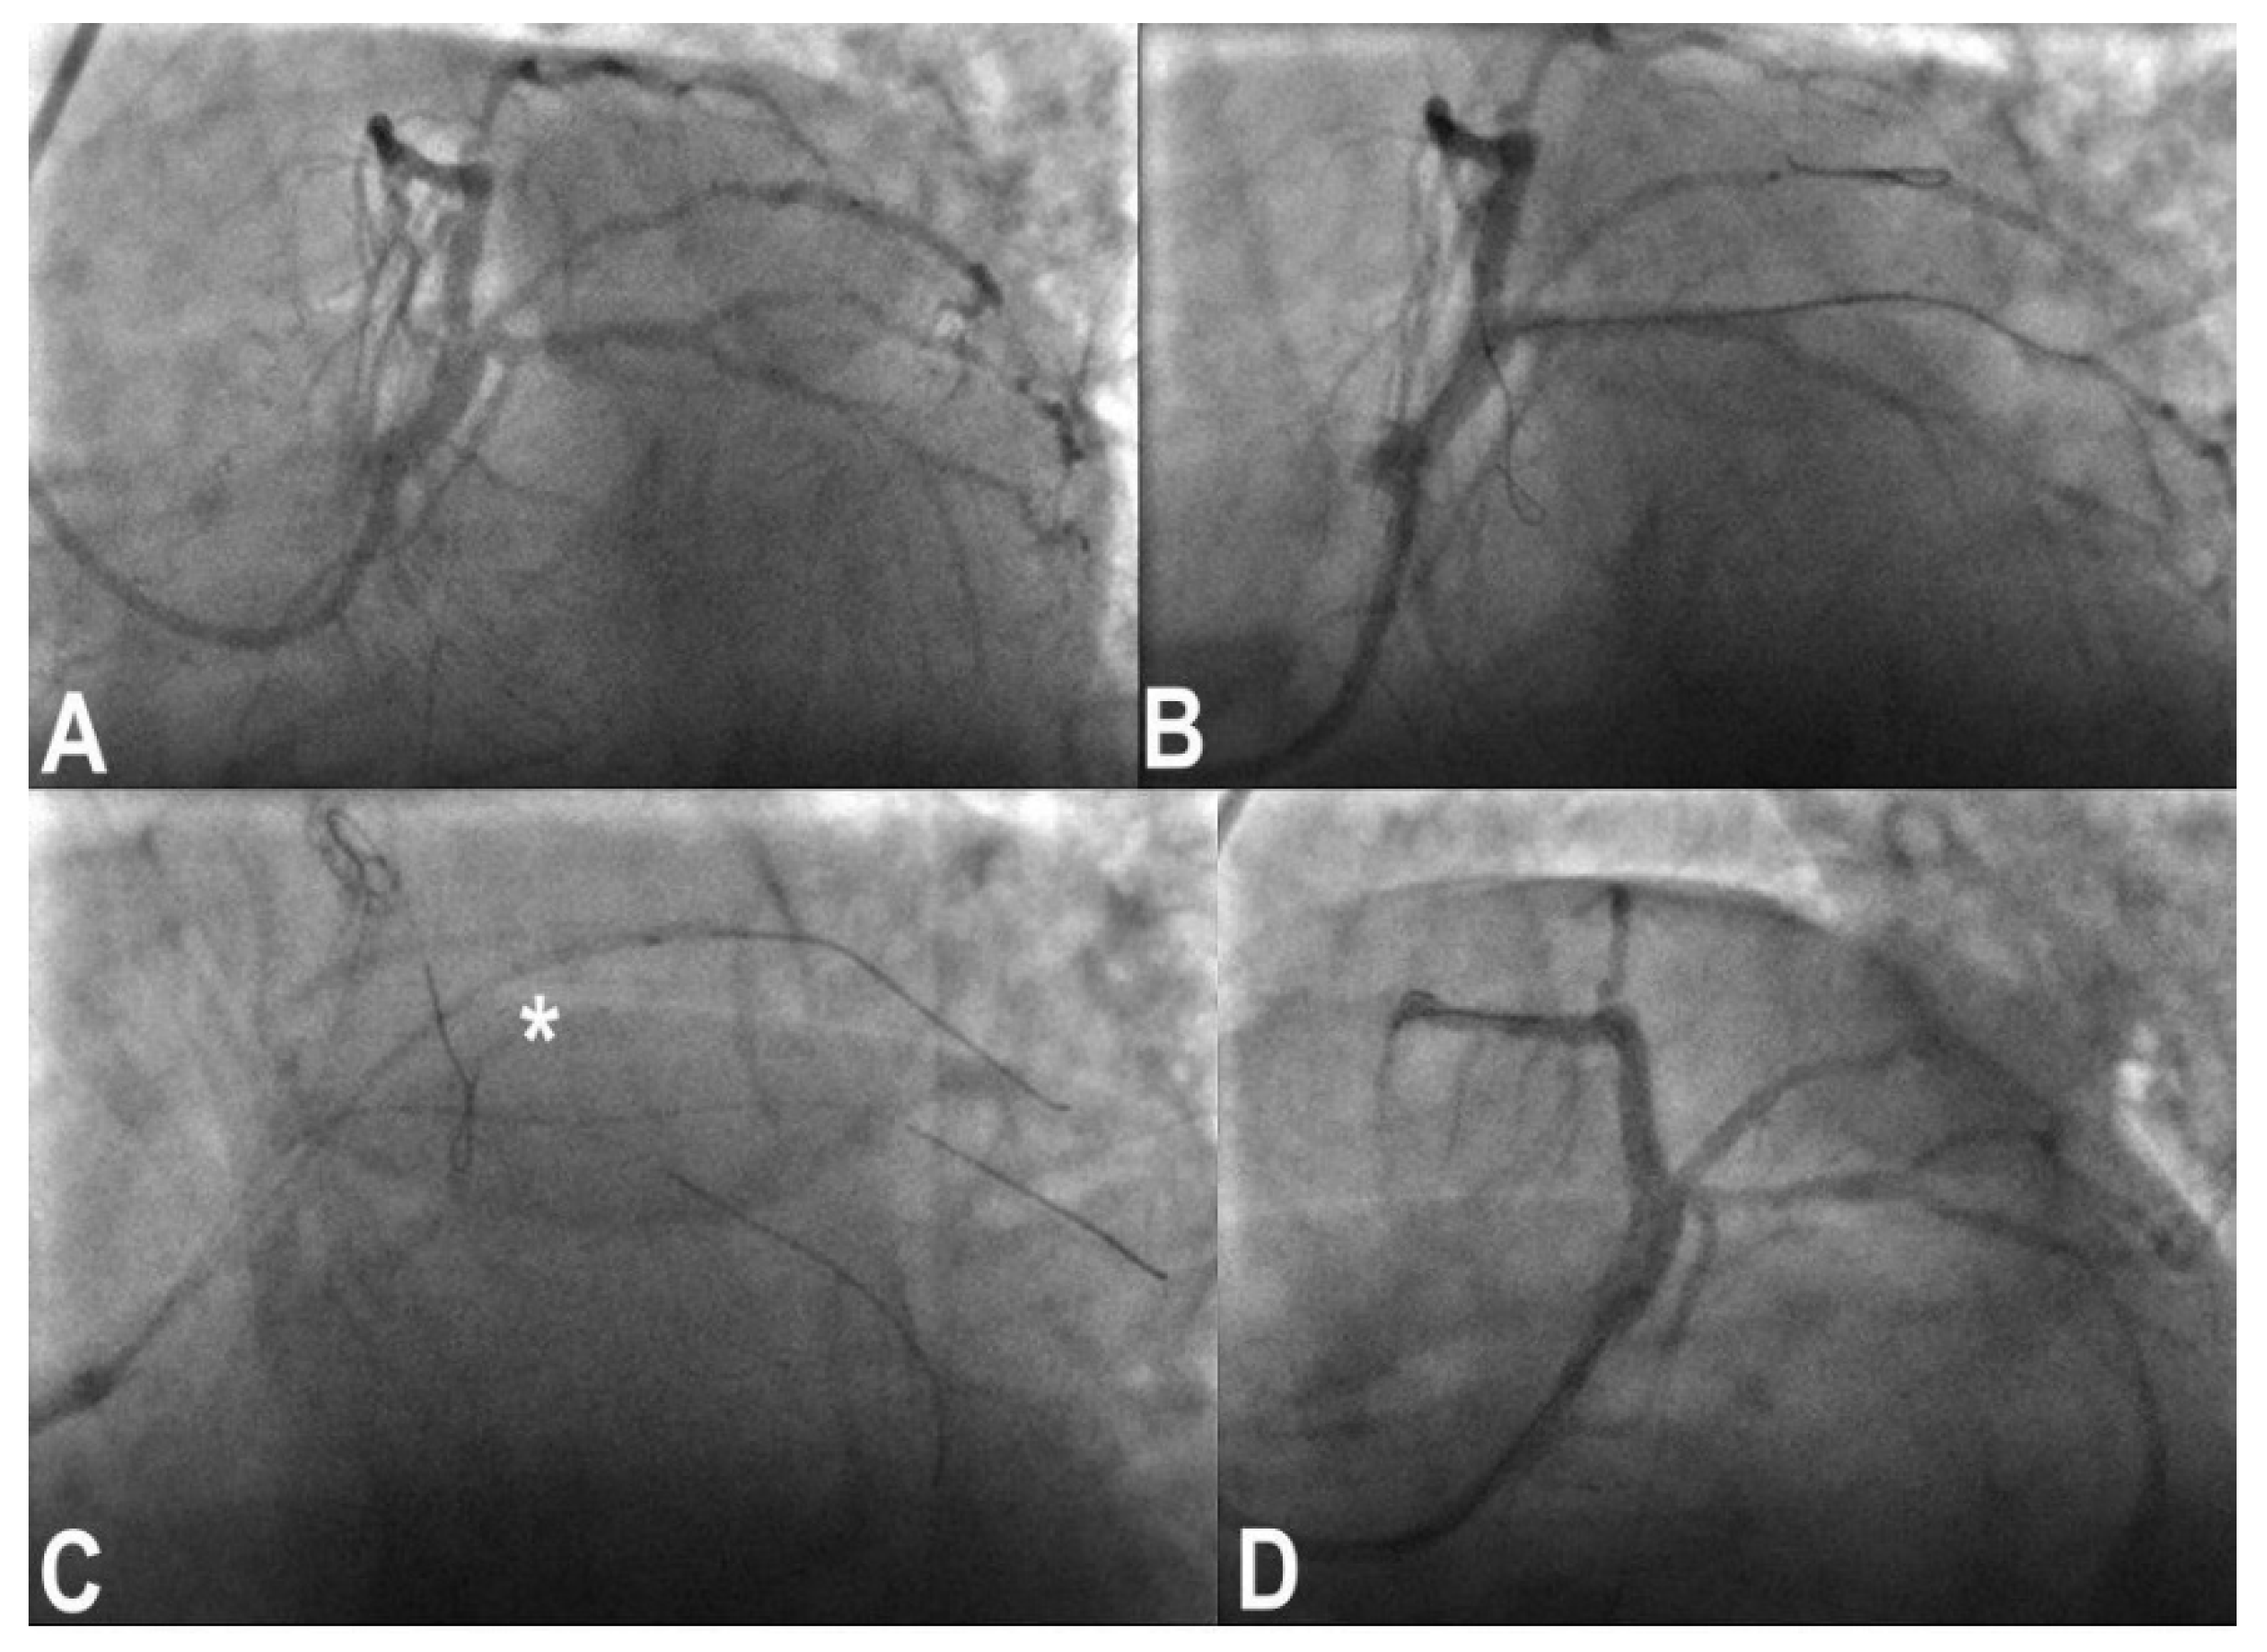

3.6. Perforation/Vessel Rupture

3.7. Wire Entrapment and Fracture

- Rigatelli, G.; Zuin, M.; Roncon, L. Unexpected huge post-stenting coronary perforation during complex left main revascularization. Turk Kardiyol. Dern. Ars. 2022, 50, 66–69. [Google Scholar] [CrossRef] [PubMed]